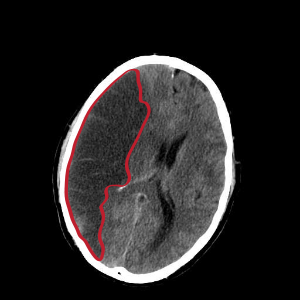

뇌경색 검사방법

우선 뇌경색 초기증상이 보인다면 내원을 하기에 전문가와 상담을 진행하게 되겠고, 진척되는 뇌경색 검사형식으로는 뇌혈관 자기 공명영상, 공명영상 촬영술, 전산화 단층 촬영, 심장 초음파, 경동맥 초음파, 뇌혈관 초음파 등의 방법으로 환자의 현재 상태를 터득해서 치료가 진행되겠습니다.

이 질병을 진단하는 검사로는 몇 가지가 연속될 수 있다고 합니다. 뇌졸중에는 뇌출혈과 뇌경색이 실재하는데, 이 양쪽 모두는 양상이 다르며 무엇이냐에 따라서 치료 절차도 상이하기 때문에 뇌경색 검사방법으로 진단을 정확히 받아서 확인하는게 선행되어야 하고 귀중가운데 하나이라고 할 수 있고요.